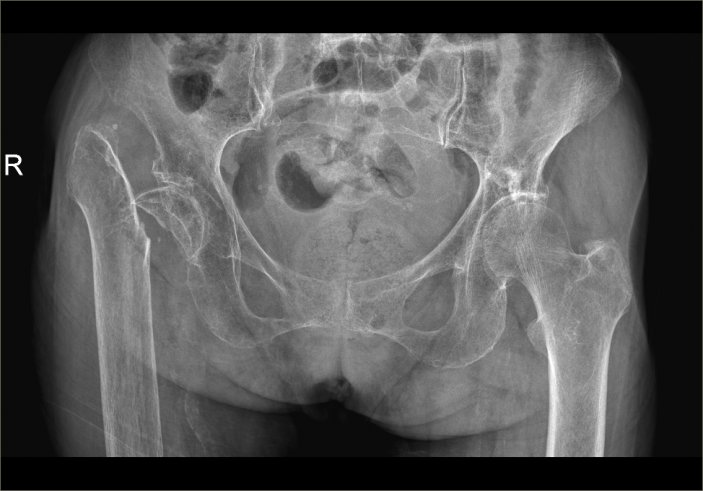

△右側(R)是賴婆婆3年前跌斷股骨術後,左側是本次手術術後。